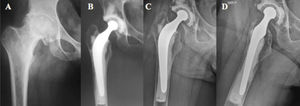

Group A: Ogee cup with cemented Charnley stem (Depuy, Warsaw, Ind, USA) (Fig. 1).

Group B: Duraloc cup with cemented Charnley stem (Depuy, Warsaw, Ind, USA).

Group C: Trident cup with cementless Accolade stem (Stryker, Mahaw, NJ, USA).